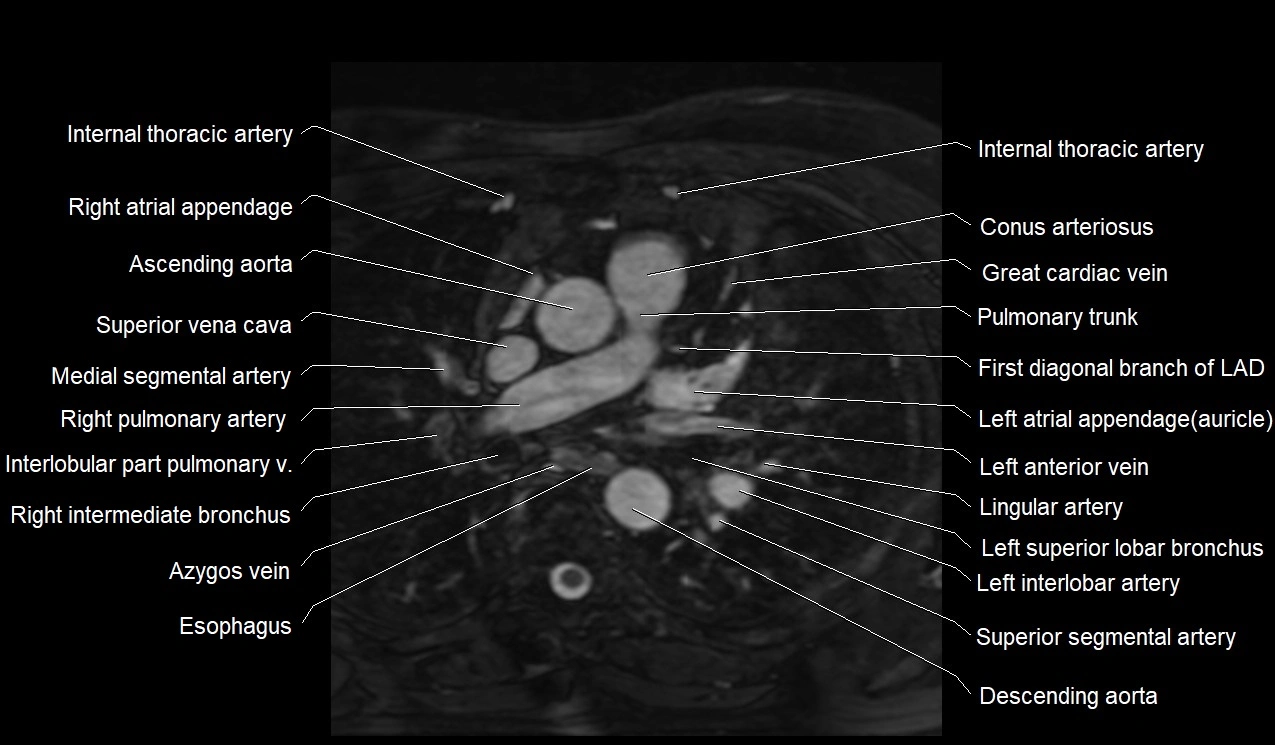

MRI image